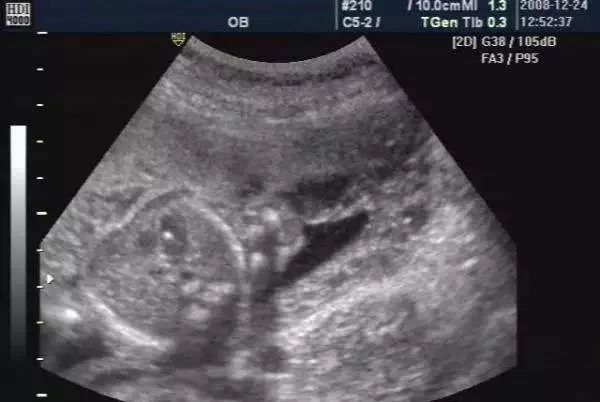

今天上午是产前门诊日,第三个进来的是小李姑娘,小李是一个输卵管梗阻的患者,做了腹腔镜手术以后怀孕的,自怀孕以后全家人把她当大熊猫一样供着,依从性倒是非常好,按时产检一项检查也不敢落下,现在已经怀孕24周了,是来做四维彩超的,来时笑容可掬,可这四维做过以后就愁容满面了,原来她的B超单上提示胎儿左心室有强光点,她担心胎儿有心脏病,吓得眼泪直在眼眶里打转。

小李姑娘,以前B超检查受机器因素影响,胎儿左心室强光点根本不可能看到,现在医院B超机器都先进了,医生的技术也提高了,以前看不到的能看见了,但结果让很多准妈妈非常担心。其实胎儿心室内点状强回声是一个声像图表现,而不是一种心脏畸形,更不是胎儿心脏异常的超声诊断,在临床上很常见,发病机制目前尚未明确,有以下几种可能:

心内强回声对大部分胎儿而言无重要临床意义,你宝宝的情况是左心室内强回声光点。心室内强回声光点在孕中期是很常见的情况,是心脏腱索内的钙化,对胎儿的生长和发育没有影响的,到孕晚期大多数有可能自己消失的,左心室强回声斑是比较常见的,这么解释你可能会更理解:有很多有问题的孩子,就是有畸形的孩子也会有左心室强回声斑,但是有左心室强回声斑的孩子未必就有问题,一般来说,胎儿只是心室有强光点,其它系统没有异常,畸形的可能不大。